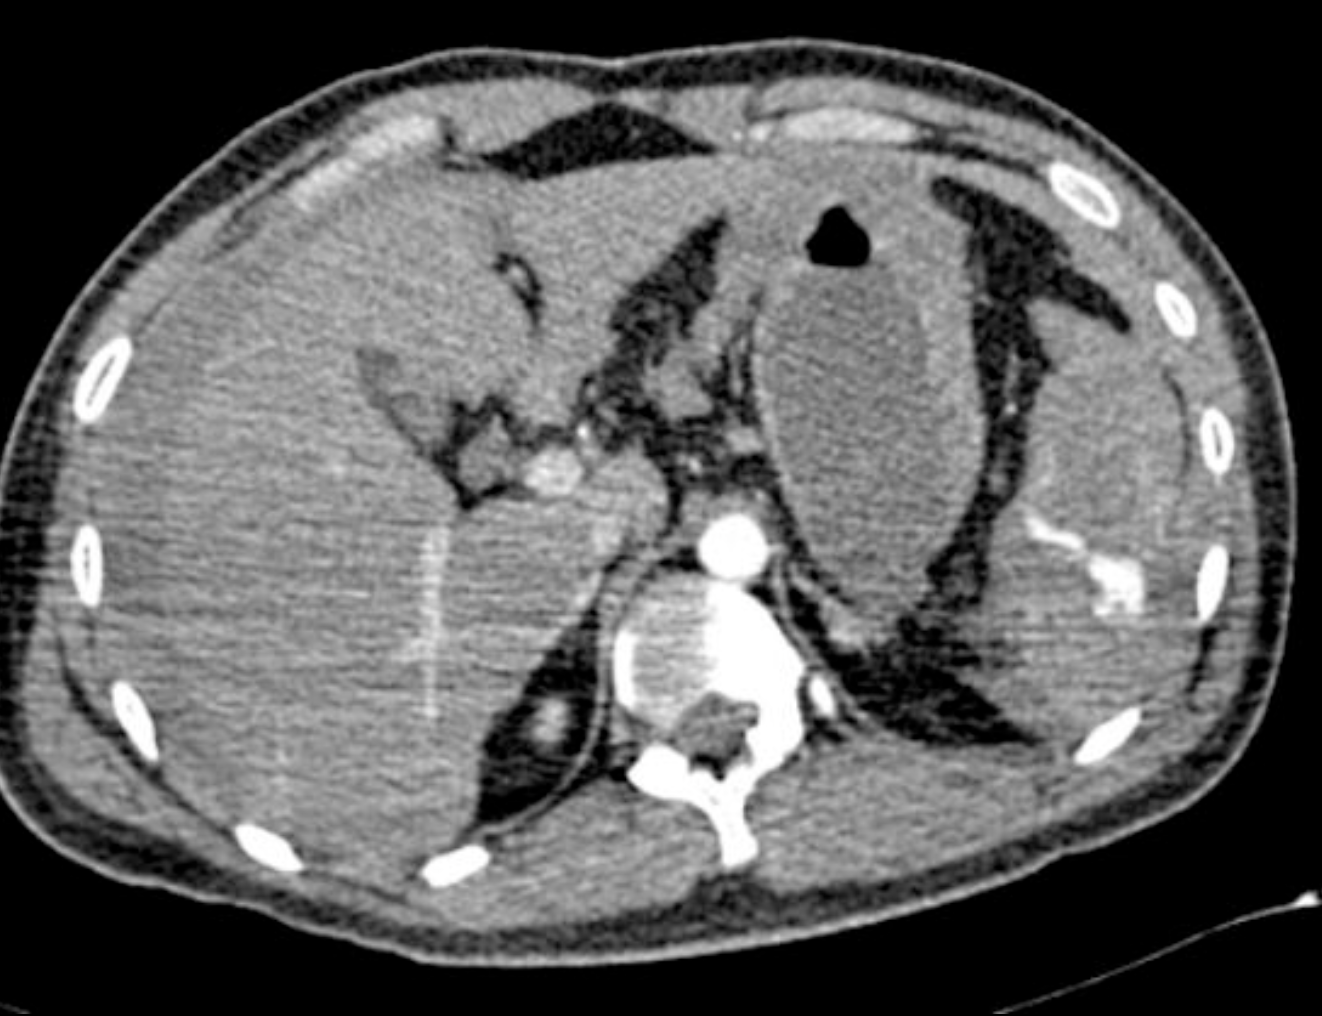

There is an intraparenchymal haematoma/laceration measuring > 5 cm which extends to the splenic hilum. Further splenic laceration noted inferiorly. Trace of perisplenic haematoma and free fluid in the pelvis. The overall appearances are in keeping with a grade 3 splenic injury in accordance with the American Association for the Surgery of Trauma (AAST) splenic injury grading.

No bone fractures or injury to other organs. Chest was clear.